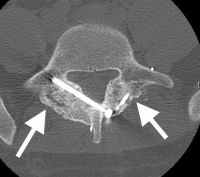

(Click to Enlarge Image) CT scan of pars fracture of L5. White arrow points to fracture. Thisadolescent had 4 months in brace and continued to have pain upon return toactivity.